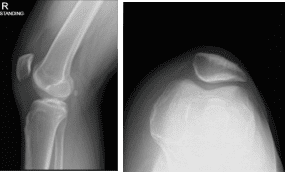

He has been complaining of knee pain despite conservative management in the form of physical therapy and anti-inflammatory medications. The patient presented X Ray for his right knee that showed no significant degenerative changes. There are no fractures.

Right knee X-ray complete with Patella